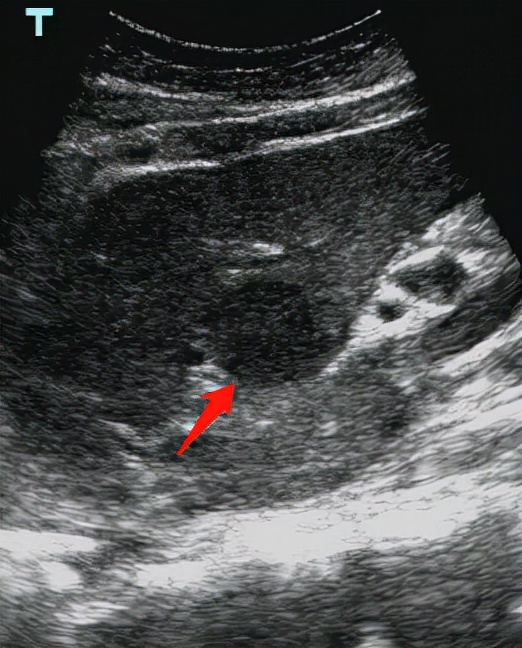

肾脏透明细胞癌

除了常见的肝脏肿瘤以外,胆囊、胰腺、脾脏、肾脏的占位都是具有重要意义的。